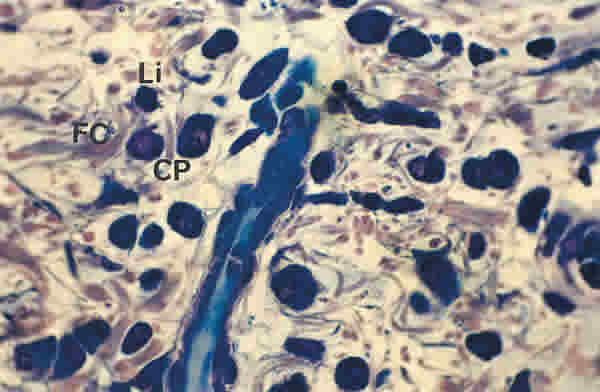

Figura 18

BIOPSIA EN UN PACIENTE CON SS1-GRADO I. EL TEJIDO CONECTIVO QUE RODEA A LA GLÁNDULA LAGRIMAL TIENE UN MODERADO NÚMERO DE FIBRAS DE COLÁGENO (FC), ESCASO NÚMERO DE LINFOCITOS (Li) Y ABUNDANTES CÉLULAS PLASMÁTICAS (CP). TINCIÓN AZULES DE RICHARDSON. MAGNIFICACIÓN ORIGINAL X100.